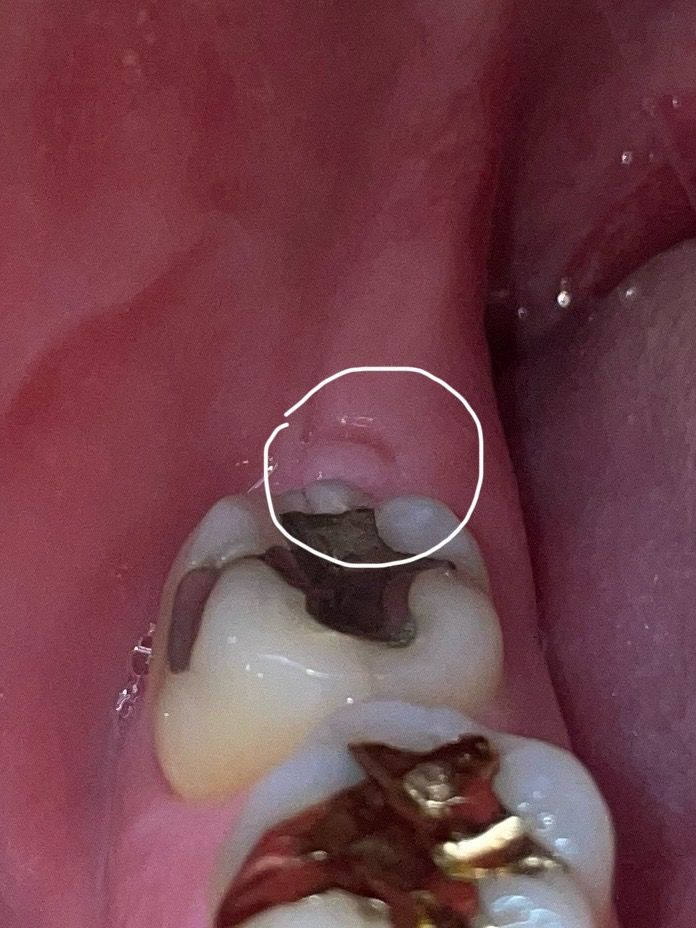

오른쪽 아래 매복 사랑니 발치 후 어금니 뒤 잇몸에 이상한 작은 혹 같은 게 생기고 통증이 있는데 크기가 점점 커지는데 이게 원인이 무엇일까요? 치과에 가니까 그냥 뭐 잇몸이 씹혀서 그렇다 괜찮다 이러는데 통증도 심하고 크기도 커지고 원인인 뭔지 원래 사랑니 발치 후 1년 지난 시점부터 생겨서 종양이나 암이나 안 좋은 질환일 수도있나요? 사진이랑 파노라마 사진 첨부합니다

저부위는 잇몸이 아물면서 생긴현상입니다. 큰 문제가 잇는건 아니니 너무 걱정하지 않으셔도 됩니다.

발치를 하고 난 다음에 해당부위가 아물면서 잇몸에 특정형태가 남아있을수 있습니다. 감염이 되지 않은것이라면 크게 문제가 되지 않기때문에 해당부위를 자극하지 않는것이 좋습니다.

사진상 크게 문제가 되어 보이는 부분이 있지는 않으나, 만약 해당부위가 더 커지고 통증이 심해지는 경우에는 절개하여 제거가 필요로 될수 있기에 치과 진료를 받길 권합니다.

단순 염증에 의한 붓기로 보이지만 사진만으로 진단을 할 수는 없으니 치과로 가보시는 게 좋겠습니다.

잇몸이 자라면서 해당부위 과증식된 것이 아닐까 싶습니다 특별히 엑스레이상으로는 문제가 없어보입니다